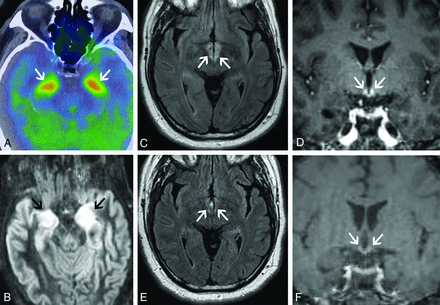

Typical imaging findings of limbic encephalitis include T2 hyperintensity and swelling of the mesial temporal lobes with FDG avidity on PET (Fig 2A, -B), sometimes with associated enhancement. These findings can also involve other parts of the limbic system. For example, paraneoplastic limbic encephalitis can have striking involvement of the hypothalamus and mammillary bodies with relative sparing of the remaining limbic system (Fig 2C–F). Sometimes limbic encephalitis can have a masslike appearance that can be mistaken for tumors such as low- or high-grade gliomas or even lymphoma (Fig 3A–C). The imaging findings in such cases can dramatically improve with treatment, and FDG hypometabolism may be seen after recovery (Fig 3D–F). Overall, limbic encephalitis has more complex imaging features than previously appreciated and should be considered even in cases that do not involve typical areas such as the hippocampus and amygdala. Atypical patterns of involvement can be seen in nonparaneoplastic limbic encephalitis as well.1,6

Classic limbic encephalitis (A and B). A 75-year-old healthy man presented with abrupt onset of memory loss and staring spells over several days. CSF analysis was positive for LGI1 autoantibodies. FDG-PET/CT axial image (A) shows marked hypermetabolism in the bilateral mesial temporal lobes (A, arrows). Axial double inversion recovery MR imaging image (B) shows corresponding increased T2 signal in both mesial temporal lobes (B, arrows). Atypical limbic encephalitis (C–F). A 29-year-old man with a history of resected nongerm cell testicular cancer presented months after treatment with worsening memory, diminished executive function, hypogonadism, and hypothyroidism. CSF analysis showed increased total protein but was otherwise normal. Axial FLAIR (C) and coronal T1-weighted postcontrast (D) images show abnormal T2 signal in the hypothalamus (C, arrows) and enhancement of the mammillary bodies (D, arrows). He was diagnosed with paraneoplastic limbic encephalitis with atypical involvement of the hypothalamus and mammillary bodies. He opted for observation with symptomatic improvement over months. Follow-up MR imaging shows improved mild residual hypothalamic T2 signal (E, arrows) and decreased enhancement of the mammillary bodies (F, arrows).

Limbic encephalitis mimicking a tumor. A 31-year-old man presented after being found unconscious while doing repair work on his home. He had multiple neurologic symptoms, including impaired thermoregulation, hypersexuality, and depression. Axial FLAIR (A) and coronal T1-weighted postgadolinium (B) images show extensive increased T2 signal and masslike enhancement centered in the region of the hypothalamus (A and B, arrows). The findings were initially considered worrisome for a neoplastic process, such as lymphoma, versus an inflammatory lesion, such as lymphocytic hypophysitis. Biopsy of this region showed a nonspecific macrophage-rich demyelinating lesion with no evidence of tumor. He was later found to have anti-Ma2 serum positivity and a mediastinal germ cell tumor. Images of the brain from his staging FDG-PET/CT show asymmetric FDG uptake in the left mesial temporal lobe (C, arrows), separate from the affected regions on his MR imaging. He was treated with chemotherapy and high-dose corticosteroids with gradual improvement in his symptoms. Axial FLAIR (D) and coronal postgadolinium (E) MR imaging obtained 1 year later show marked improvement in the prior findings, with mild residual hypothalamic T2 signal (D, arrows) and mild enhancement of the tuber cinereum (E, arrows). His subsequent FDG-PET/CT shows decreased FDG avidity in the previously involved left mesial temporal lobe (F, arrows). Ultimately, his intracranial findings were consistent with limbic encephalitis rather than malignancy.